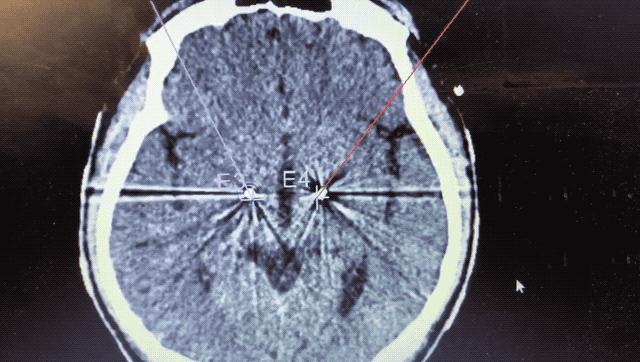

順利檢測到典型的核團信號后,再次植入刺激電極到相應位置,測試后即可完成單側的電極植入。對側只需借助機器人再次定位,并將檢測電極、刺激電極依次植入,最后,還需將刺激器植入患者胸前皮下。根據(jù)術后CT顯示,本手術雙側植入電極的位置與術前規(guī)劃路徑完全吻合,患者開機后,起搏器會開始沿刺激電極向患者核團實施高頻電刺激,以減輕疾病癥狀,提高患者的生活質量。

術后CT顯示雙側電極植入位置與規(guī)劃完全吻合